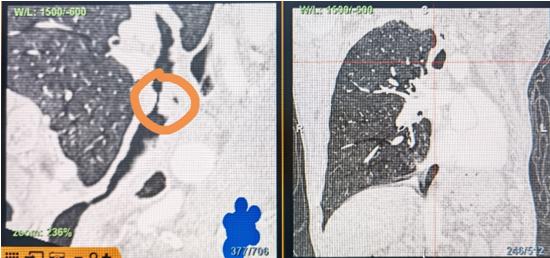

时间就是生命!了解患者病情后,欧阳海峰立刻启动气道梗阻紧急救治通道,协调院前转运,急诊快速入院流程。9日凌晨患者入院,胸部CT显示,现存唯一的呼吸通道在右主支气管处,狭窄处仅约3毫米,患者命悬一线!

运用呼吸介入技术,软硬镜结合快速开通气道,是患者目前唯一可行的治疗方案,手术刻不容缓!但存在麻醉后气道完全塌陷闭合、大出血、窒息等巨大风险。患者此前接连转诊3家医院,均建议保守支持治疗或转院。欧阳海峰详细了解患者病史,全面评估影像检查结果后,决定尽快进行手术,组织医护团队对患者进行持续密切监测,充分保障其术前安全。

1月10日,在麻醉手术中心全力配合下,欧阳海峰带领呼吸介入团队,历时40分钟快速置入硬质支气管镜、铲切肿瘤,并顺利植入全覆膜TTS支气管金属支架。患者气短症状即刻缓解,为患者赢得了宝贵的后续治疗机会。